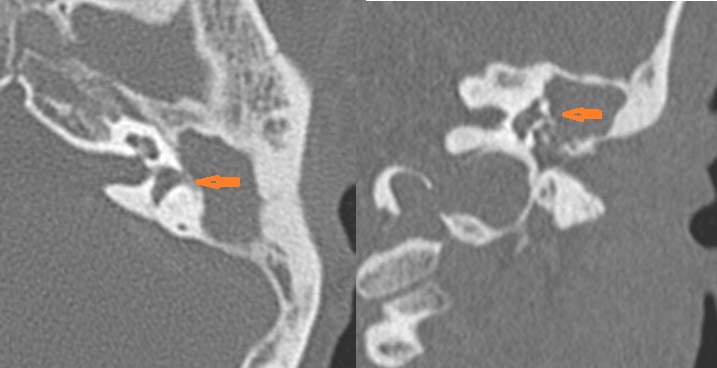

External auditory canal bone is eroded. [Yes/No]

The petrotympanic fissure is eroded. [Yes/No]

The ossicles, in particular the incus long process, the incudostapedial joint and stapes are eroded or displaced. [Yes/No]